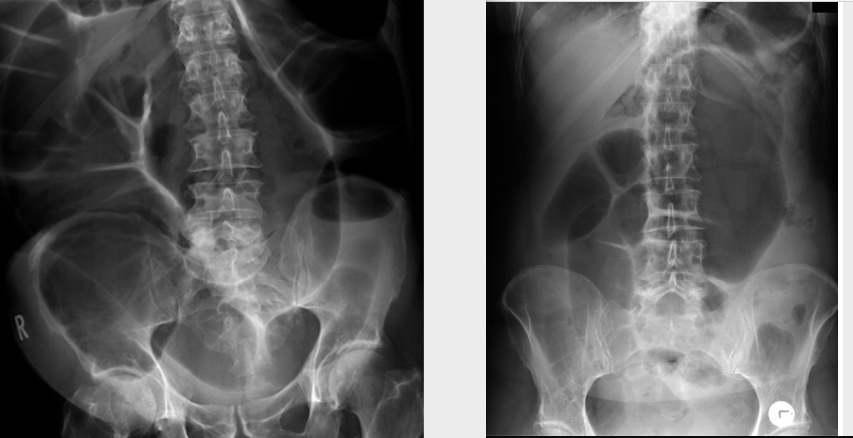

Small bowel obstruction - features

Centrally located multiple dilated loops of gas filled bowel (arrowheads)

Valvulae conniventes (arrow) are visible - confirming this is small bowel

This abdominal X-ray demonstrates multiple dilated loops of bowel with clear valvulae connivente markings. The large bowel is collapsed. **This indicated small bowel obstruction.**

39

This abdominal X-ray shows multiple loops of dilated bowel with a loss of bowel markings **indicating large bowel obstruction. **